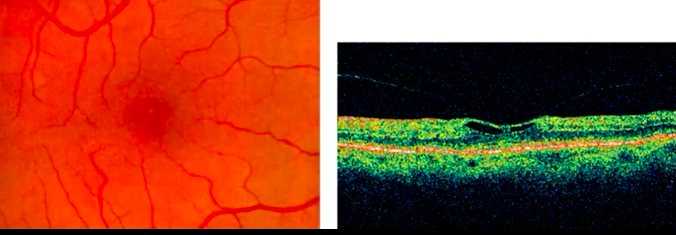

As alterações encontradas no exame físico e nos exames complementares são justamente as explicitadas no enunciado: à fundoscopia vemos perda da transparência retiniana com uma coloração mais acinzentada (geralmente mais temporal à fóvea), perda do brilho foveal e acúmulo de material cristalino na retina interna. Existe uma outra alteração bem característica na fundoscopia que é a presença de vaso em ângulo reto (literalmente um vaso formando um ângulo reto em direção à fóvea).

À angiofluoresceinografia temos hiperfluorescência com vazamento tardio em região perifoveal (geralmente temporal). Na tomografia de coerência óptica é possível identificar cistos afetando diferentes camadas da retina interna, com diminuição da espessura macular central.

OCT: CAVITACAO NA RETINA INTERNA; INTERRUPCAO DA ZONA ELIPSÓIDE DA RETINA EXTERNA